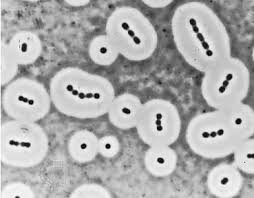

spore

只有

- Bacillus

- 好氧格蘭氏陽性桿菌

- Clostridium

- 厭氧格蘭氏陽性桿菌

Clostridium (梭狀桿菌,G+)

- 絕對厭氧

- 清創,截肢

- Spore

- 腸胃道好朋友

C. perfringens (產氣梭狀桿菌)

- 好大一隻

C. tetani (破傷風)

- 雞腿狀

C. botulinum (肉毒梭孢桿菌)